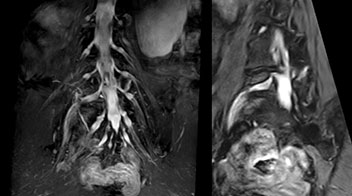

“In such case, we would then browse through axial T2-weighted MR images slice by slice and mentally reconstruct the actual situation based on both radiculography and MRI. Fortunately, NerveVIEW can now very well show nerve courses and presence of nerve compression or edema in one single image series.” “We have often seen NerveVIEW directly depict details of the nerve compression that were not observed by radiculography. Therefore, we think that with NerveVIEW we can reduce the number of invasive examinations, especially for some patients with lumbar plexus symptoms.”

“Before NerveVIEW, diagnosis by MRI alone was sometimes difficult, unless there was a strong suspicion based on clinical symptoms,” says Shoji Yabuki, MD, DMSc, Orthopedic surgeon at Fukushima Medical University School of Medicine. “This is why we routinely perform selective lumbosacral radiculography (nerve root block) and x-ray in such cases. However, radiculography can only depict nerves as far as the contrast agent reaches. When a nerve is distorted by compression, the contrast agent will not pass through this compressed area, preventing us from evaluating the full nerve compression.”

“The intra-luminal signal of veins, especially around the intervertebral space, can be suppressed well with NerveVIEW. As a result, we can easily observe the detailed nerve structure around the posterior ganglion,” he says. “This is why we use 3D NerveVIEW for intraforaminal stenosis and extraforaminal stenosis/herniation (lateral disc herniation). On the other hand, if herniation is suspected to exist inside the dorsal root ganglion (DRG), balanced TFE or ProSet-FFE is applied. NerveVIEW is not suitable for evaluating the median type of herniation.” The SE-EPI DWI-based method for MR neurography works well for large FOV exams like whole-body MRI, but focal examination of nerves is often limited by the attainable spatial resolution (both inplane and slice direction) and geometric distortion. “3D NerveVIEW achieves higher in-plane resolution – close to our other routine spine sequences – and the source images can be used instead of adding a fat-suppressed T2-weighted sequence,” Tanji says.

According to Tanji, methods such as ProSet FFE, STIR or 3D VISTA are anatomically nonselective because background signals, for instance from blood vessels, often interfere with nerves, which hampers evaluation of details, especially at the peripheral side of the nerves.